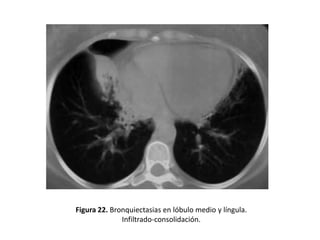

• Otros hallazgos demostrables mediante un estudio

BQ serían: (figuras 19-22).

– Pérdida de volumen o áreas de consolidación

Figura 22. Bronquiectasias en lóbulo medio y língula.

Infiltrado-consolidación.

Signos indirectos • Otroshallazgos demostrables mediante un estudio con TAC y que pueden constituir signos indirectos de BQ serían: (figuras 19-22). – Enfisema – Irregularidad de la pared bronquial – Atelectasias – Pérdida de volumen o áreas de consolidación

Figura 22. Bronquiectasiasen lóbulo medio y língula. Infiltrado-consolidación.